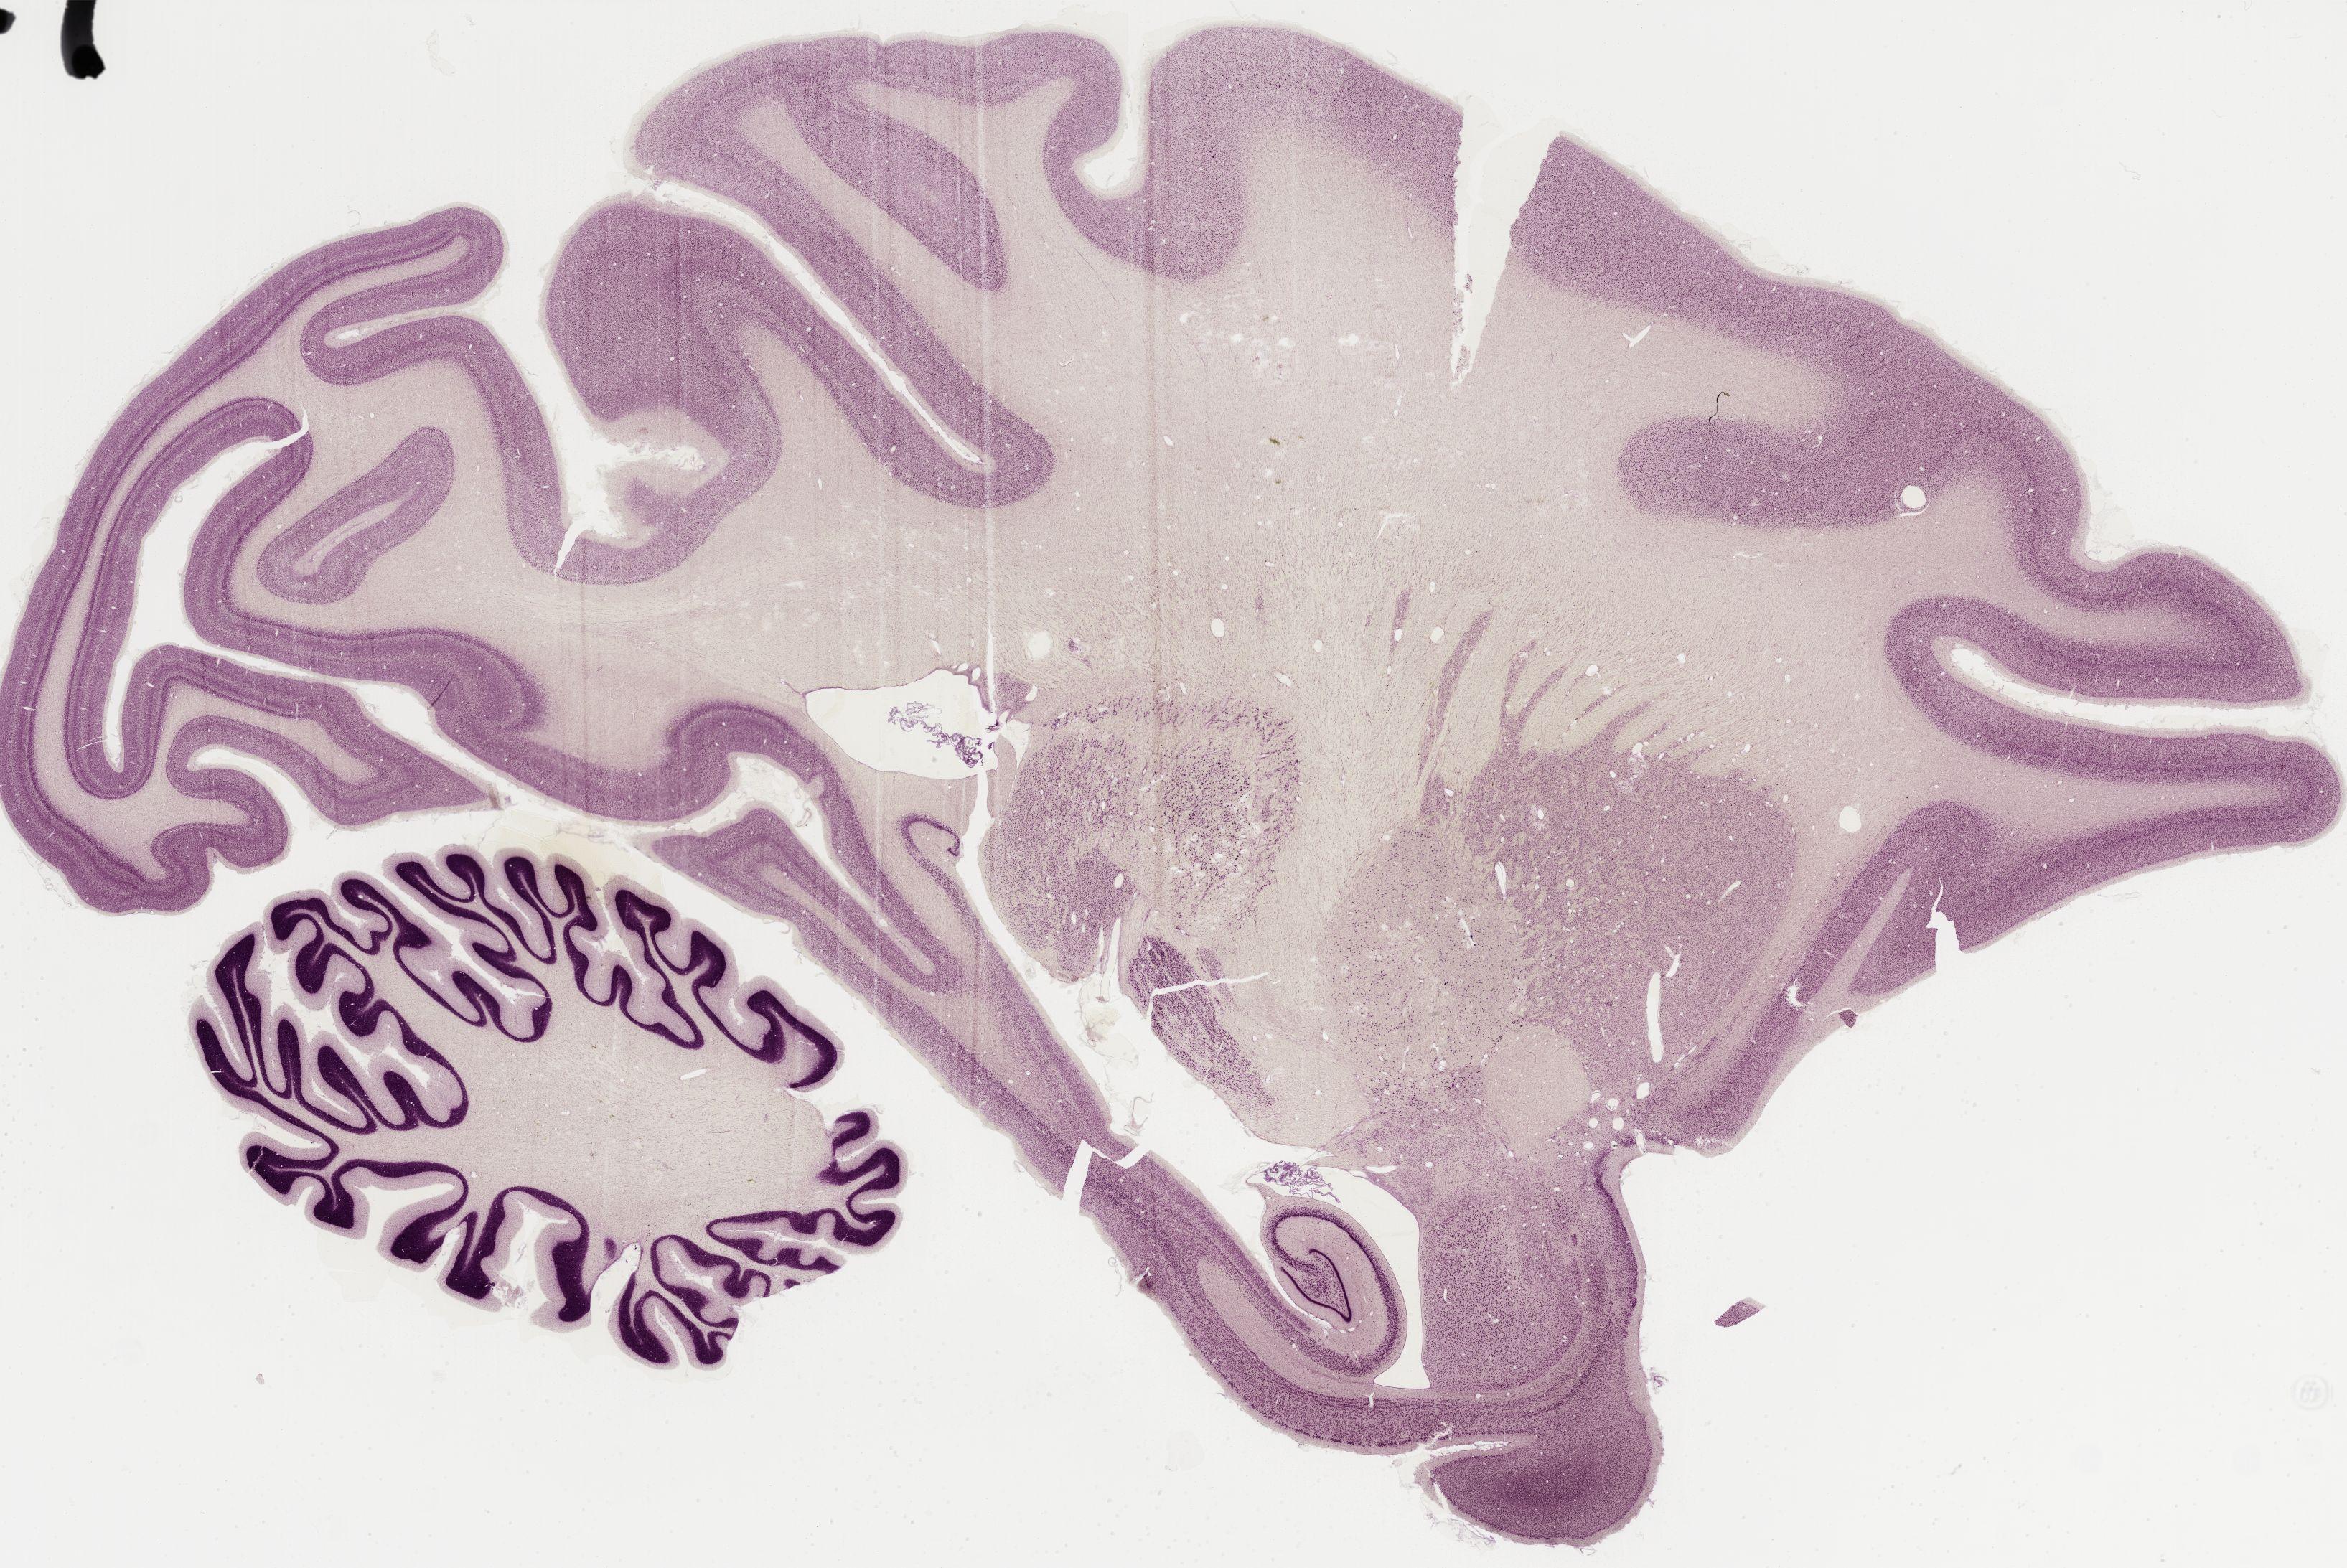

Datasets -> Macaca Mulatta -> Nissl, sagittal, histo, Whole-Brain, adult

[ Metadata ]   ·   Source: Edward G. Jones

Displaying Sections 161 thru 200 of 295 Sections for this Dataset

0366 - labeled